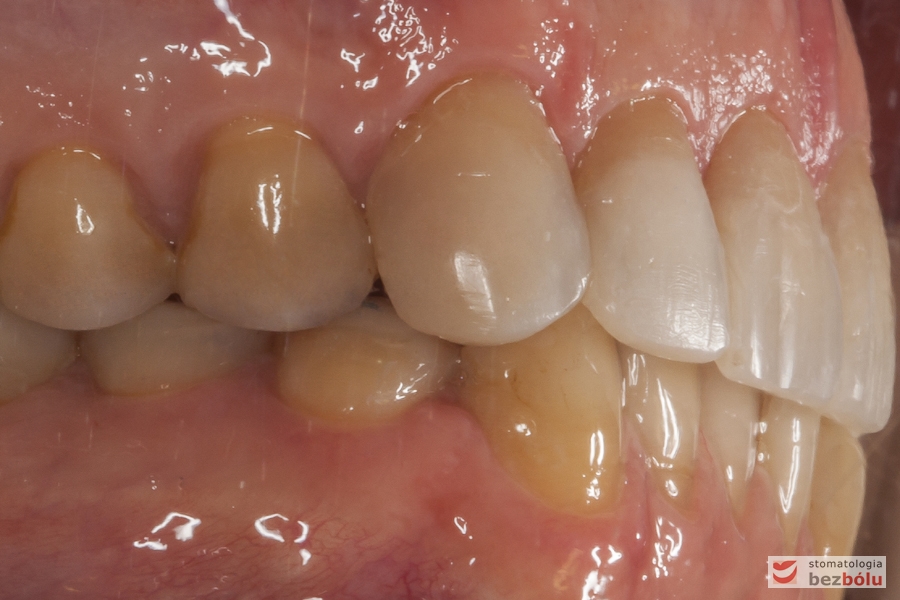

Zęby w zwarciu - strona prawa, przebarwienia świadczące o chorobie szkliwa (hypoplazja)

Zęby w zwarciu – strona prawa, przebarwienia świadczące o chorobie szkliwa (hypoplazja)